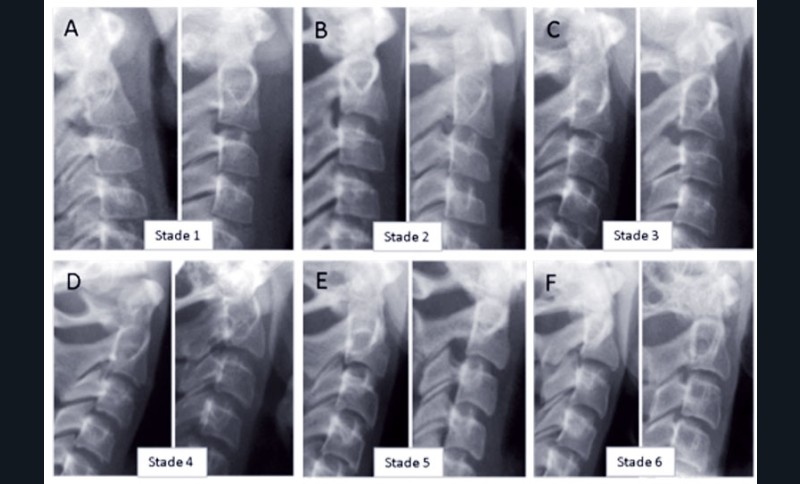

Cette méthode, mise au point par Lamparski en 1972 et simplifiée par Baccetti et McNamara, permet de déterminer le moment optimal de début de traitement. En évaluant la maturation des vertèbres cervicales sur des téléradiographies de profil grâce à leur forme il est possible de situer le patient sur sa courbe de croissance. Selon la forme des corps vertébraux de C2, C3 et C4 et de leur bord inférieur on distingue 6 stades de maturation vertébrale (fig. 1 et 3).